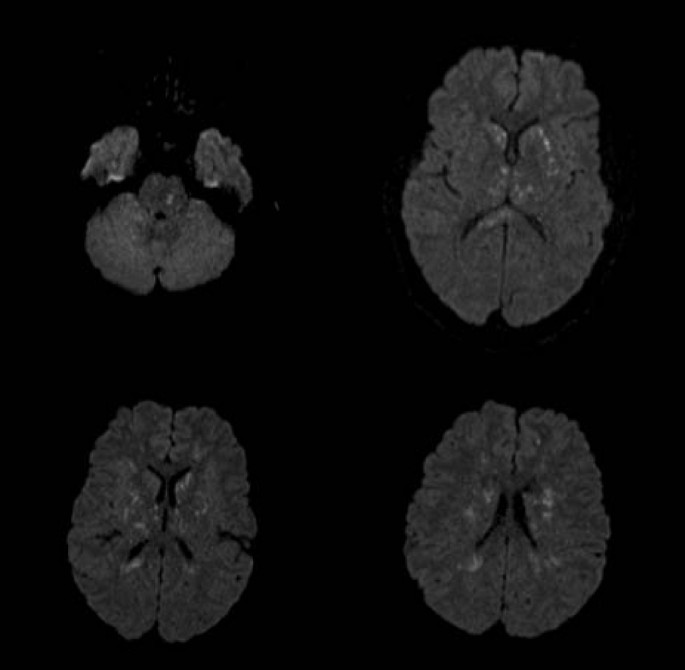

Nearly all long-bone fractures are accompanied by some form of fat embolism. The rare complication of clinically significant fat embolism syndrome, however, occurs in only 0.9-2.2% of cases. The clinical triad of fat embolism syndrome consists of respiratory distress, altered mental status, and petechial rash. Cerebral fat embolism causes the neurologic involvement seen in fat embolism syndrome. A 19-year-old African-American male was admitted with gunshot wounds to his right hand and right knee. He had diffuse hyperactive deep tendon reflexes, bilateral ankle clonus and decerebrate posturing with a Glasgow Coma Scale (GCS) score of 4T. Subsequent MRI of the brain showed innumerable punctate areas of restricted diffusion consistent with "starfield" pattern. On a 10-week follow up he has a normal neurological examination and he is discharged home. Despite the severity of the neurologic insult upon initial presentation, the majority of case reports on cerebral fat embolism illustrate that cerebral dysfunction associated with cerebral fat embolism is reversible. When neurologic deterioration occurs in the non-head trauma patient, then a systemic cause such as fat emboli should be considered. We describe a patient with non-head trauma who demonstrated the classic "starfield" pattern on diffusion-weighted MRI imaging.

While fat embolism occurs in nearly all long-bone fractures, the incidence of clinically significant fat embolism syndrome (FES) after long-bone fractures is only 0.9% to 2.2% [1, 2]. The clinical triad of FES consists of respiratory distress, altered mental status, and petechial rash. Cerebral fat embolism (CFE) consists of multiple microembolic infarcts giving a picture of a "starfield" pattern in diffusion-weighted MRI imaging (DWI) [2, 3]. Neurologic symptoms can be transient and widely varied from a diffuse encephalopathy to focal deficits, all the way to neurological devastation and death. Though often non-fatal, patients typically require extended hospital stays for supportive care as their symptoms resolve [4]. We describe a patient with non-head trauma who presented with coma and demonstrated the "starfield" pattern on (DWI).

A 19-year-old African-American male without past medical history was admitted with gunshot wounds to his right hand and right knee. He was intubated upon arrival secondary to generalized tonic-clonic seizure activity. He was found to have an open proximal phalanx fracture of the right ring finger and an open right lateral femoral condyle fracture. Initial CT of the head was unremarkable for intracranial abnormalities, and continuous EEG ruled out non-convulsive status epilepticus. He was taken to the operating room for debridement and immobilization of both open fractures and then admitted to our intensive care unit (ICU). On neurological exam, patient was unarousable with eyes closed and spontaneous blinking. His pupils were dilated but responsive to light. Petechiae were observed in the nasal aspect of the left eye. He had normal occulocephalic, corneal, and cough reflexes. He had diffuse hyperactive deep tendon reflexes, bilateral ankle clonus and decerebrate posturing with a Glasgow Coma Scale (GCS) score of 4T. Subsequent MRI of the brain showed innumerable punctate areas of restricted diffusion within the basal ganglia, thalami, splenium of the corpus callosum, deep white matter, frontoparietal cortex and pons (Figure 1). CT angiogram of the head and neck showed patency of major cervical and intracranial vessels and no evidence of vasculitis. Urine toxicology was positive for methamphetamine and cannabis. Transthoracic echocardiography showed no cardiac abnormalities and revealed no embolic source. On a 10-week follow up he has a normal neurological examination and he is discharged home.

The outcome of patients with FES who receive supportive care generally leads to resolution of pulmonary, neurological, and dermatological involvement with mortality of less than 10%. The majority of case reports on CFE illustrate that cerebral dysfunction associated with CFE is reversible [2–4]. Ryu et al. described findings on DWI on six patients with CFE secondary to large bone fractures. Level of consciousness in these series varied from drowsiness to coma. The DWI images showed hyperintense dot-like lesions disseminated in the brain consistent with a "starfield" pattern and Fluid-Attenuated Inversion Recovery (FLAIR) sequence MRI showed confluent hyperintense lesions in the white matter. The lesions were distributed mainly but not exclusively in the bilateral border-zone areas. Five out of six patients had either full neurological recovery or mild disability within ten days of admission [3]. Gregorakos et al. describe two cases involving teenage males suffering from prolonged coma secondary to CFE and lower extremity fractures from motor vehicle collisions (MVC). MRI showed multiple areas of increased signal intensity in the cerebral white matter in the first patient and diffuse high signal intensity in periventricular and subcortical white matter in the second one. Despite prolonged coma for 40 days, both of these patients completely recovered and their repeat MRI showed resolution of lesions [4]. Parizel et al. describe a teenage female who fractured her left tibia secondary to MVC. MRI T2 weighted images, two days after the accident, showed punctate foci of high signal intensity in subcortical white and gray matter (basal ganglia and thalami). DWI showed a "starfield" pattern. This patient had full neurological recovery by one week and repeat MRI four weeks post MVC revealed disappearance of signal abnormalities [2].

The majority of CFE cases have reversible sequela. There is a correlation between the MRI findings of CFE patients and their clinical manifestations according to Takayashi et al. Cases with good outcome had complete resolution of high-intensity lesions on subsequent MRI studies [5]. DWI should be performed in non-head trauma patients who either present or develop altered mental status, as CFE needs to be considered in these patients. The "starfield" pattern is commonly associated with good prognosis despite severity of the neurologic insult upon presentation.